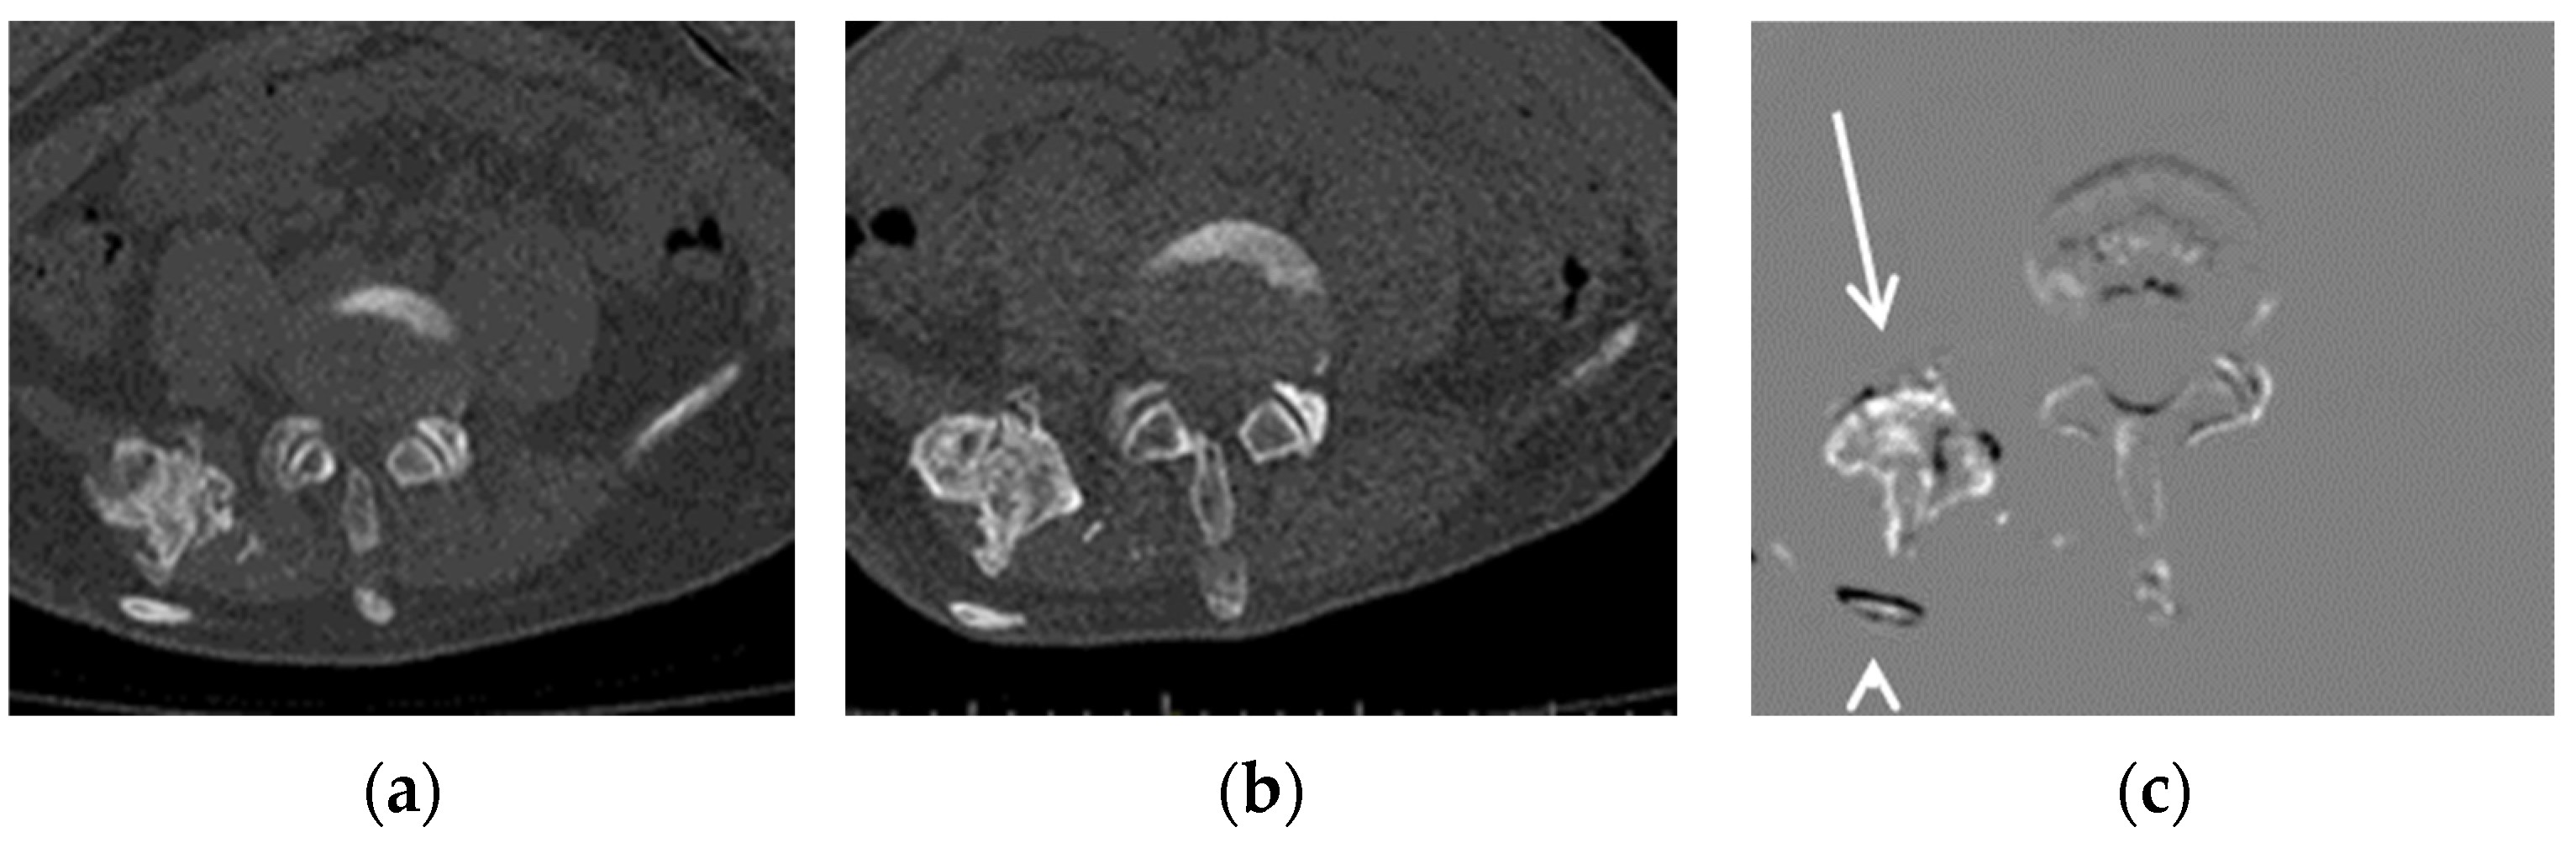

Figure 2.

Example of a growing lesion. CT images of a 16-year-old FOP patient: (a) previous CT image, (b) current CT image, and (c) TS (subtraction) image. The growing lesion near the ilium (arrow) is difficult to detect in the current CT image, but is clearly visible in the TS image. The dorsal rib of this lesion (arrowhead) is shown due to misregistration.